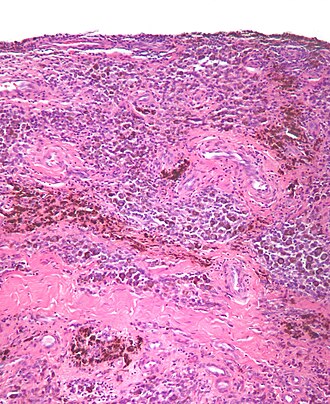

Template:Px Diffuse tenosynovial giant-cell tumour. H&E stain. | |

| LM | nodules composed of cells with abundant cytoplasm & pale nuclei, multinucleated giant cells, hemosiderin-laden macrophages, foam cells |

Features:[10]

- Subsynovial nodules composed of cells with:

- Abundant cytoplasm.

- Pale nuclei.

- Multinucleated giant cells.

- Hemosiderin-laden macrophages.

- Foam cells.

The soft tissue sections show nodules with abundant hemosiderin-laden macrophages and multinucleated giant cells. Nuclear atypia is not identified. Mitotic activity is not apparent.